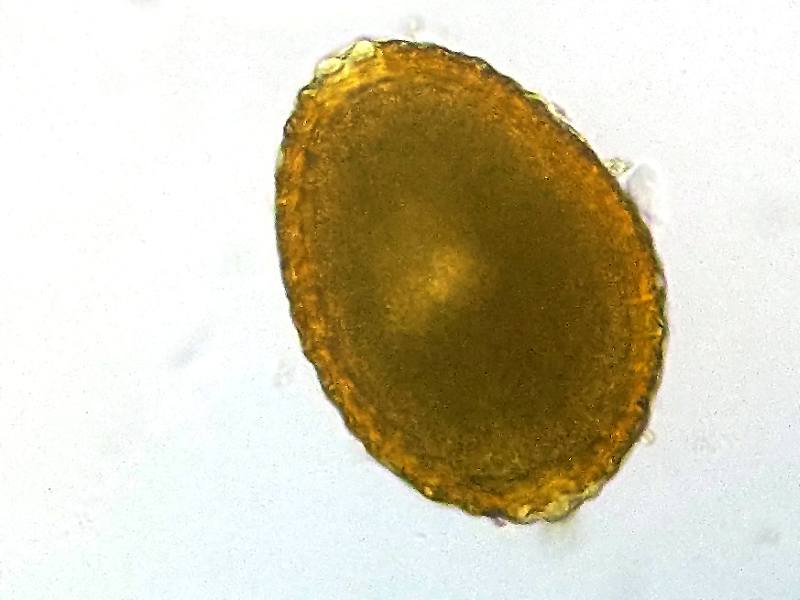

Darmwürmer nachzuweisen, ist in aller Regel nicht sonderlich kompliziert. Hierfür wird eine Kotprobe von einem Tierarzt unter dem Mikroskop untersucht. Meist sind in der Probe Eier der Würmer zu finden. Wirksame Mittel gegen Wurmbefall kann Ihnen Ihr Tierarzt empfehlen. Eine Nachbehandlung mit homöopathischen Mitteln bei starkem Wurmbefall kann mit den homöopathischen Präparaten Nux vomica D6 und Mercuris solubilis D12 über das Trinkwasser erfolgen.